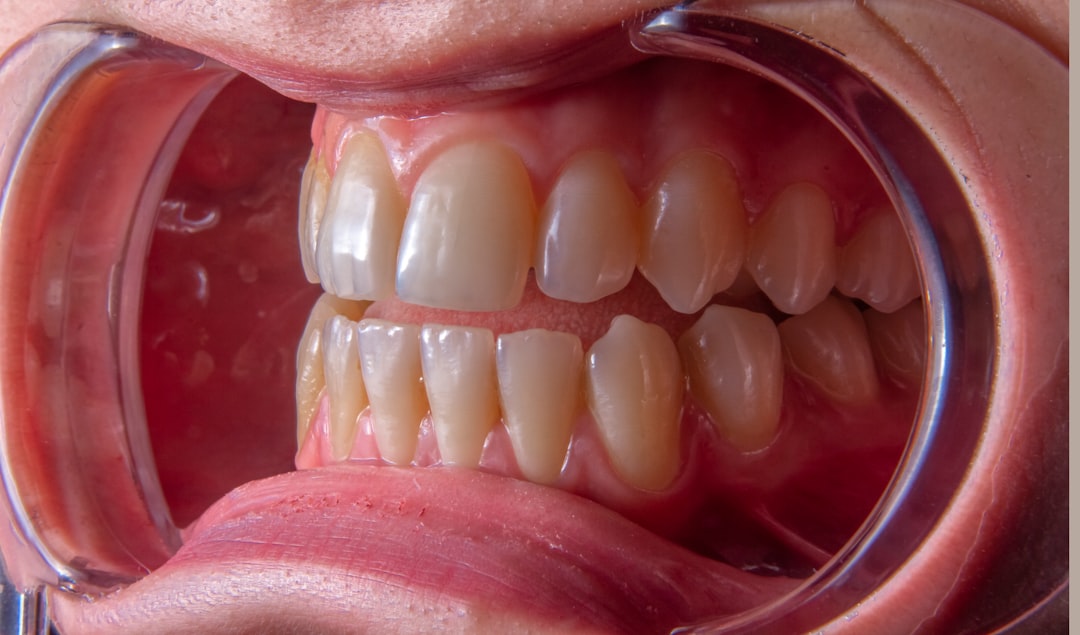

급성 후두개염은 목구멍 뒤쪽에 있는 후두개가 염증으로 인해 부풀어 오르는 질환으로, 주로 인후염이나 바이러스 감염으로 발생합니다. 이 상태는 특히 어린이에게 더 흔하며, 급성 후두개염은 기도를 막아 호흡 곤란을 초래할 수 있어 주의해야 합니다. 어린이의 경우 기도가 좁기 때문에 더욱 위험합니다. 아이가 호흡이 힘들어 보일 때는 반드시 의사와 상담해야 합니다. 이런 질환을 잘 이해하는 것이 회복의 첫걸음이 될 것입니다.

급성 후두개염의 증상은 다양합니다. 가장 흔한 증상으로는 심한 목 통증과 목소리 변화가 있습니다. 또한, 아이들이 특히 짖는 기침을 보이는 경우가 많은데, 이는 후두개가 부풀어 기도가 압박받고 있다는 신호입니다. 이런 기침은 엄마 아빠를 불안하게 만들죠. '왜 아이가 이렇게 기침을 할까?'하는 생각이 든다면, 반드시 전문의의 진료를 받아보세요.

또한 고열이 동반되기 때문에, 땀을 흘리며 불편해할 수 있습니다. 이때 못 먹거나 음료수조차 마시지 못하는 경우가 많아지므로, 수분 섭취를 잊지 않는 것이 중요합니다. 급성기에는 기도가 붓고 염증이 심해져서 호흡이 어색해지는 경우도 있습니다. 이렇게 되면 숨을 쉬기 어려워지죠. 다시 생각해보면, 급성 후두개염은 단순한 질환이 아니라는 점을 깨달을 수 있습니다.

신속하게 대응하는 것이 중요합니다. 아이가 숨을 쉴 때 쌕쌕거림을 보이거나, 피부가 파랗게 변하는 시점에 이르렀다면 즉시 응급 서비스에 연락해야만 합니다. 이런 경과를 통해, 급성 후두개염이 얼마나 심각한 질환인지 알 수 있습니다.